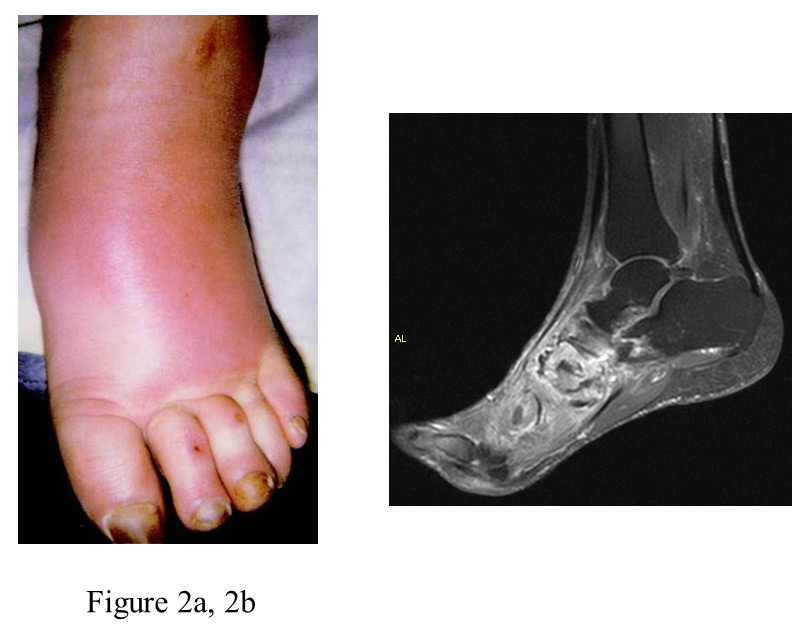

Figure 2

a: clinical aspect of an acute Charcot foot stage 1.

b: MRI (T1w, fat suppressed, with contrast media) showing bone marrow oedema and impact fractures in the Lisfranc joints, a fluid collection with circular structure (equivalent to synovial fluid leakage and/or fracture hematoma) in the tarsal region, and adjacent soft tissue oedema (bright appearance).